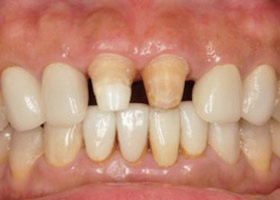

1. 術前口內正面照、局部X光片。

2. 上顎明顯暴牙、下顎參差不齊。